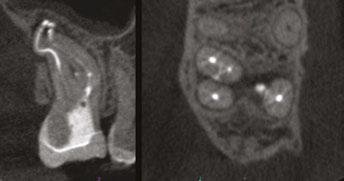

Figure 3: Second maxillary molar with external root resorption (ERR) with incidentally captured ERR on the lower mandibular first molar as well. When there is one tooth with resorption, be suspicious of other teeth with resorption, especially on younger patients Figure 6: No PARL on PA film. Clear PARL on scan taken with medicament Figures 4 and 5: 4. Mandibular molar with a J-shaped lesion due to endo — not a vertical root fracture. Path of least resistance happens to be through a distal perio pocket, but this is an endo-perio lesion and not a VRF. Incidentally, a mucous retention cyst was captured in the sinus. 5. Healing after bridge removal and retreatment

Figure 7: Planned-for access with the scan info on this extremely calcified canine Figures 8 and 9: 8. Deep distal split with PARL. 9. Missed buccal canal; history of previous RCT, post, crown and apico Figure 10: Retreatment consultation. PA from GD Figure 11: Scan images show a previously existing strip perforation

I’m also changing my treatment plans based on the data from my CBCT. Sometimes I look at a root canal treated PA and presume I know what I will do: a retreatment or an apico. Another recent, poignant case: a lower incisor with a previous RCT and a previous apico (Figure 9). Usually, once a tooth has had an apico, there may not be much left to offer and most of the time, the default is another apico, especially as there was very little room for an implant on the lower anteriors. I scanned the tooth and saw that a whole canal had been missed — twice! The RCT and the apico had left the buccal canal completely untouched. I changed my treatment plan based on this information!